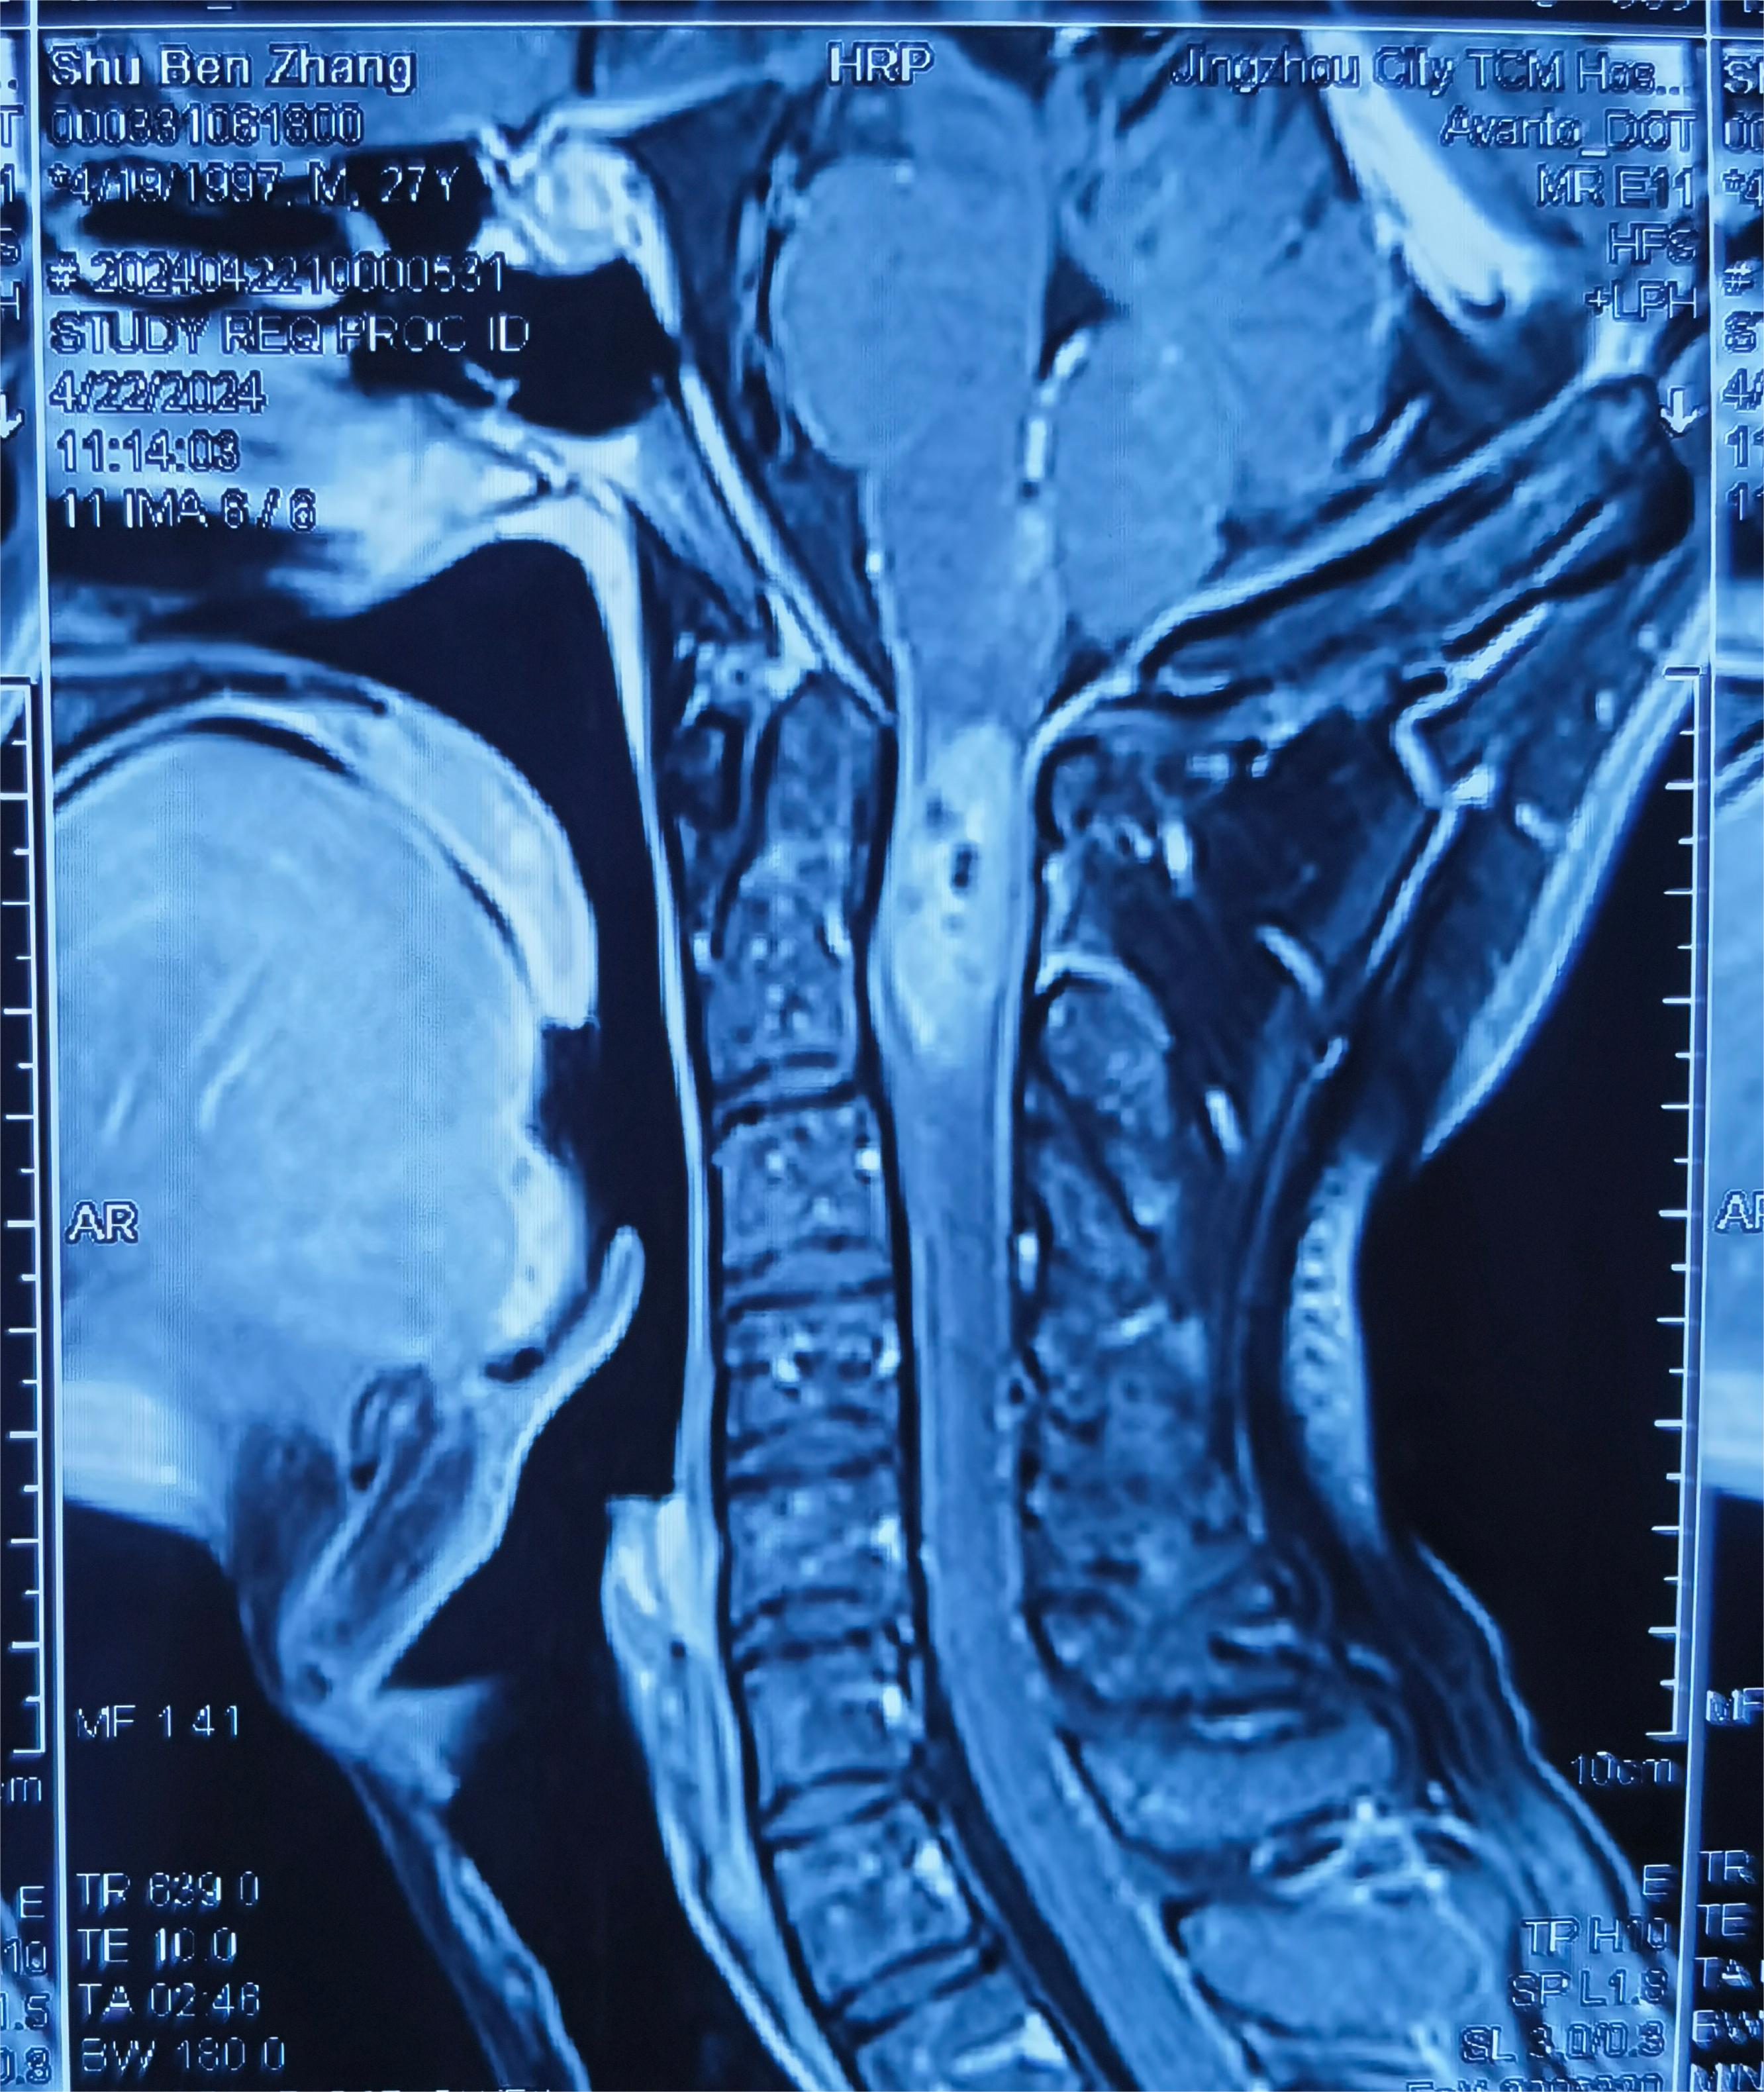

入院查头颈部MR提示C1到C2髓内占位,脊髓肿胀明显

术后MR提示肿瘤近全切除